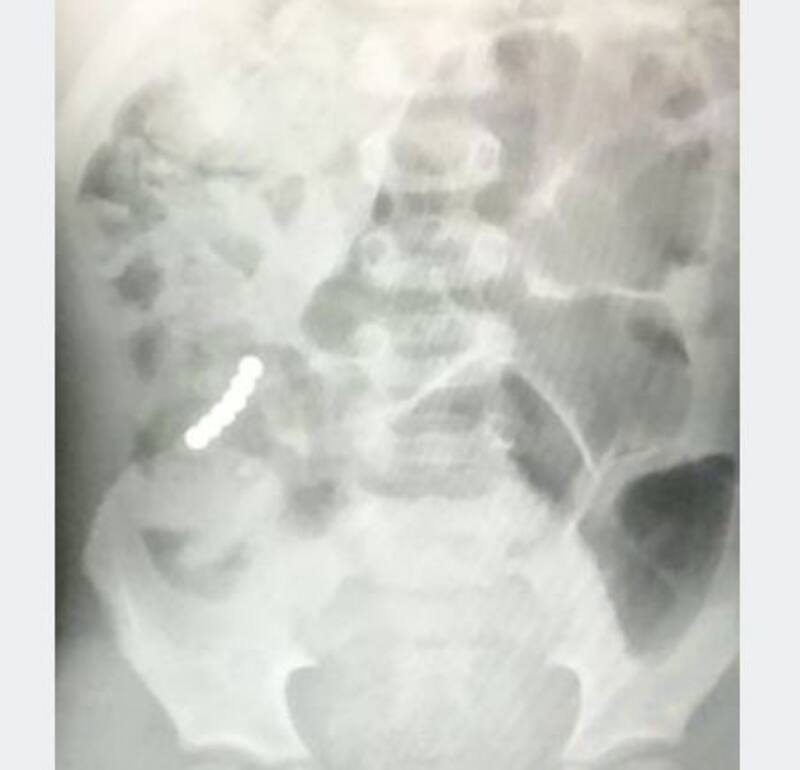

Después de esto, Mickey empezó a sentir un intenso dolor estomacal por lo que sus padres decidieron llevarlo a urgencias, ya en el hospital los doctores le tomaron una placa y notaron que en el estómago del pequeño había unos objetos extraños que le perforaron el intestino, por lo que el menor tuvo que ser intervenido de emergencia pues los pequeños objetos le habían perforado el intestino.